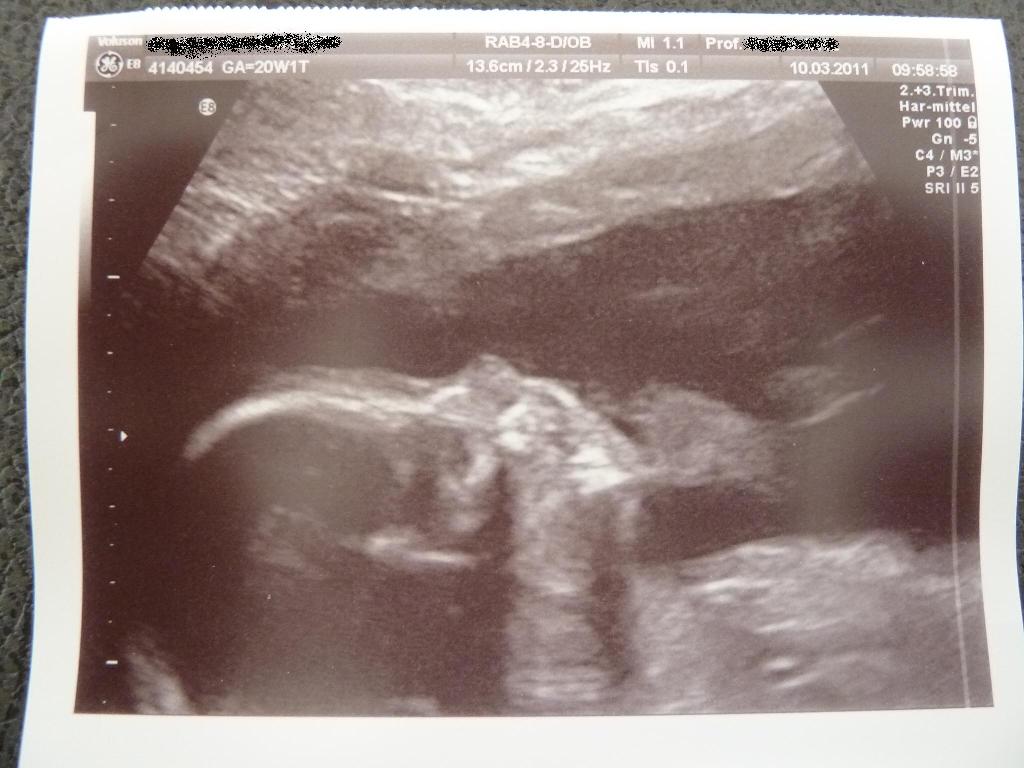

@all: die heute Feindiagnostik war zum Glück sehr angenehm.

Der kleine Mann scheint eine recht vergnügliche Behausung zu haben. Er „sitzt“ nunmehr in meinem Bauch und lässt sich durch die Gegend schaukeln. Beim Termin vor eineinhalb Wochen lag er ja noch in Schädellage. Ab und an „saß“ er im Schneidersitz drinnen und war recht gemütlich.

Der Hammer war, dass sie beim Schallen des Köpfchens den Ultraschallkopf kurz unter meinen Rippen gehalten hat. Also ganz weit oben. So riesig hatte ich mir das alles gar nicht vorgestellt.

Jedenfalls waren keinerlei Auffälligkeiten zu entdecken.

Ausgehend von der Femurlänge hat der kleine Mann eine Gesamtlänge von stolzen 22 cm. Wahnsinn, oder???

Auch die Durchblutung war vollkommen in Ordnung und sie hat dafür nur einen Versuch pro Seite und pro Seit maximal 20 Sekunden für die Messung gebraucht. War nicht schwierig. Was mich extrem erleichtert hat.

Ansonsten war der kleine Mann wie immer Fotoscheu. Er hat IMMER die Händchen vor dem Gesicht gehabt. Insofern hatten wir nicht viel vom kurzen Umschalten auf 3D. Aber süße Patschehändchen hat er, das wissen wir jetzt genau.

Bin sehr froh und erleichtert. Man hat ja doch immer ein wenig Schiss, dass doch irgendwas sein könnte.

Mein Menne war auch ganz ergriffen und stolz und froh.

Anbei noch 2 Bildchen. Auf dem einen ist das Profil, nicht sehr gelungen aufgrund der Schwierigkeiten, die der Kleine beim Fotografieren macht. Auf dem anderen ist ein Füßchen zu sehen. Das Füßchen ist immerhin schon 3,5 cm lang –Wahnsinn, oder??????????